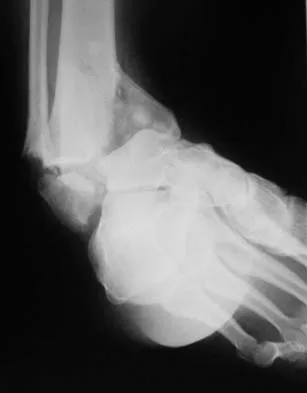

An active 47-year-old woman with rheumatoid arthritis reports forefoot pain and deformity and has difficulty with shoe wear. Examination reveals hallux valgus and claw toes. A radiograph is shown in Figure 10. What is the most appropriate surgical treatment?

Rheumatoid arthritis commonly affects the metatarsophalangeal joints, which become destabilized with time resulting in hallux valgus and dislocated lesser claw toes. The result is metatarsalgia as the dislocated claw toes "pull" the fat pad distally. Severe hallux valgus reduces first ray load, which compounds the metatarsalgia because the load is transferred to the lesser metatarsal heads. First metatarsophalangeal arthrodesis restores weight bearing medially and corrects the painful bunion. Metatarsal head resection slackens the toe tendons to allow correction of the claw toes by whatever means necessary and decreases plantar load over the forefoot. Rheumatoid arthritis in the first metatarsophalangeal joint will continue to progress if osteotomies or a Lapidus procedure are performed. Keller resection arthroplasty increases transfer metatarsalgia and reduces push-off power during gait. Flexor-to-extensor tendon transfer of the lesser toes does not address the metatarsalgia and does not correct the dislocation of the metatarsophalangeal joint. Coughlin MJ: Arthritides, in Coughlin MJ, Mann RA (eds): Surgery of the Foot and Ankle, ed 7. St Louis, MO, Mosby, 1999, p 572.